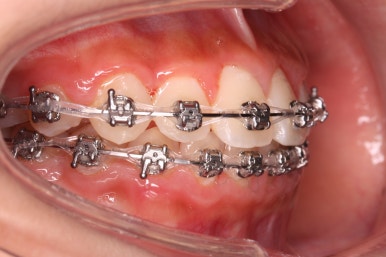

점점 가지런해지고 있는 모습이 보이실 것입니다.

악궁 확장 이후 확보된 공간은 가지러낳게 하는데 수월함을 줍니다.

다른 앵글에서의 모습입니다.

안으로 쏙 들어가 있던 앞니가 앞으로 나오게 되면서 심미적으로 좋아지는 것을 볼 수 잇습니다.